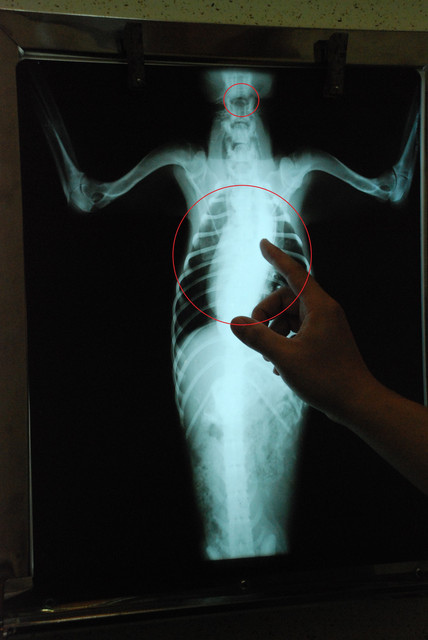

昨天夜裡,醫師緊急為虎寶拍了X光片,想要弄清楚虎寶的身體狀況。

首先,在X光片上方的圓孔是氣管被切斷的斷片。下方的原點則是虎寶的食道,食道已經整個都塞住了,這也是所謂的「巨食道症」。

x光片中的圈圈就是腸胃,裏頭一點一點的則是糞便。最後,醫師透過灌腸,讓虎寶將滿肚子的大便排出來。